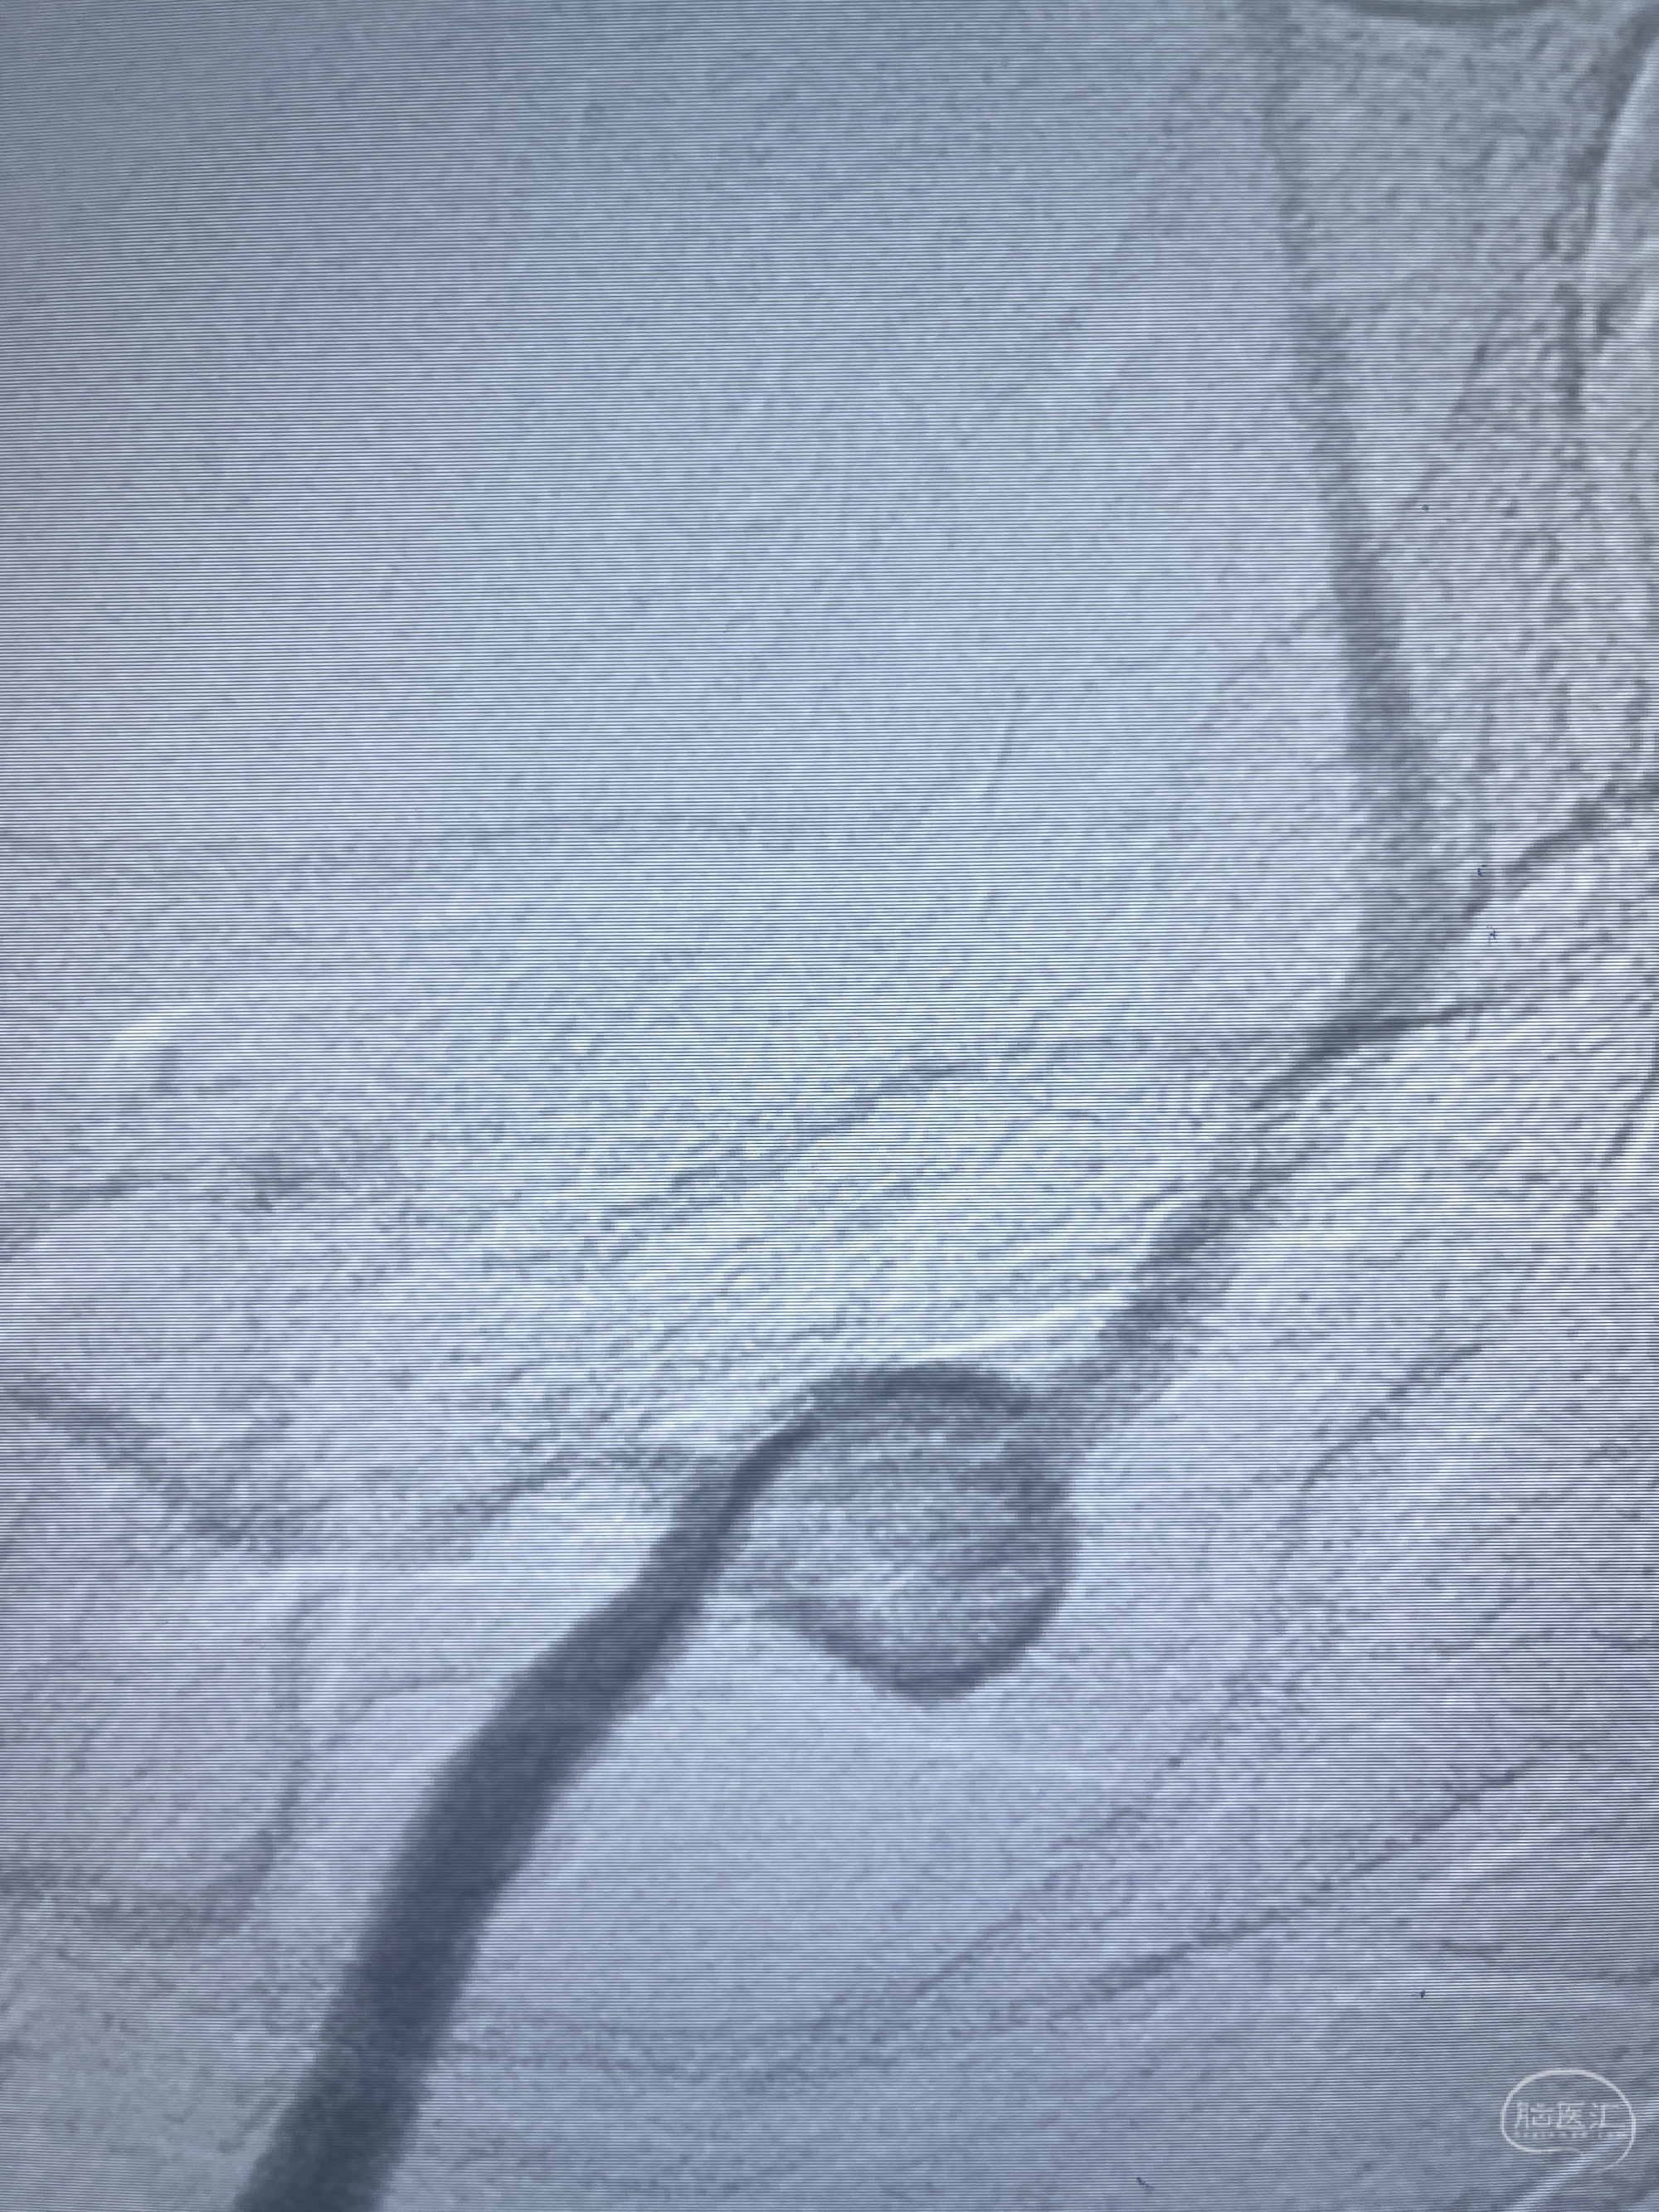

202.04.28脑血管造影:右侧大脑后动脉远段闭塞,右侧椎动脉V4段可见“囊状造影剂填充影”,大小7.64*7.65mm,可见PICA由动脉瘤发出;